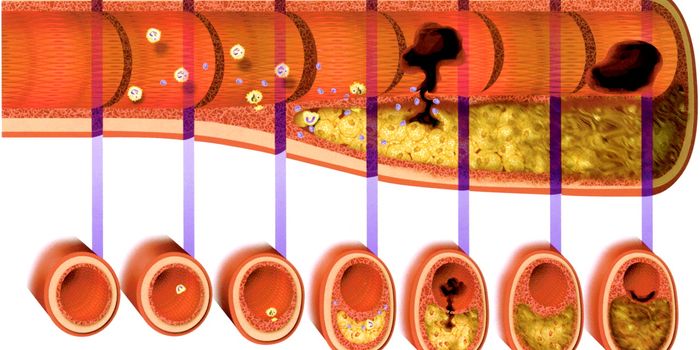

JUN 14, 2016CardiologyMedication to dissolve blood clots and various surgical procedures can be done to reverse damage done to arteries with o ...